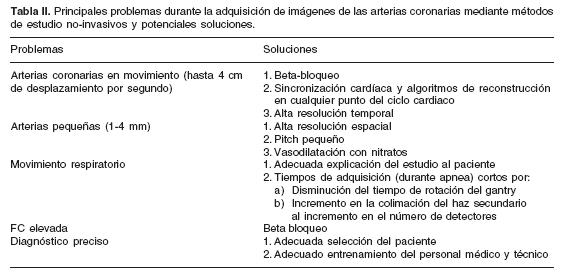

La tomografía computada (TC), inventada por Godfrey Hounsfield en 1972, ha tenido una evolución insospechada y un empleo prácticamente ilimitado.8 Mientras los sistemas de primera generación adquirían una sola imagen en aproximadamente 300 seg, en la actualidad los equipos de cuarta generación realizan la adquisición de hasta 256 imágenes en tan sólo 400 mseg, es decir 900–1,000 veces más rápidos que los aparatos de primera generación.8,9 La TC multidetector (TCMD) fue desarrollada coronaria y tomografía cardíaca. hacia finales de la década de los 90, y es considerada actualmente como el método no invasivo de elección para la evaluación vascular del tórax. Sin embargo, su papel en el estudio del corazón se encontraba limitado debido al movimiento cardíaco rápido y continuo, a la compleja anatomía cardiovascular y a las pequeñas dimensiones de las arterias coronarias (Tabla I).

Habitus del paciente. Otros factores directamente relacionados al paciente, como lo son su ritmo y FC también influyen en la calidad de las imágenes y en la presencia de artificios por movimiento. (Tabla II).

Pese a los avances tecnológicos, la resolución temporal disponible requiere una FC media menor a los 70 lpm para evitar artificios por movimiento. La calidad diagnóstica de la imagen es inversamente proporcional a la FC del paciente. 24–29 La importancia de la FC no sólo radica en el hecho de obtener imágenes de calidad diagnóstica, sino también en que la radiación es mayor en aquellos pacientes con FC altas.